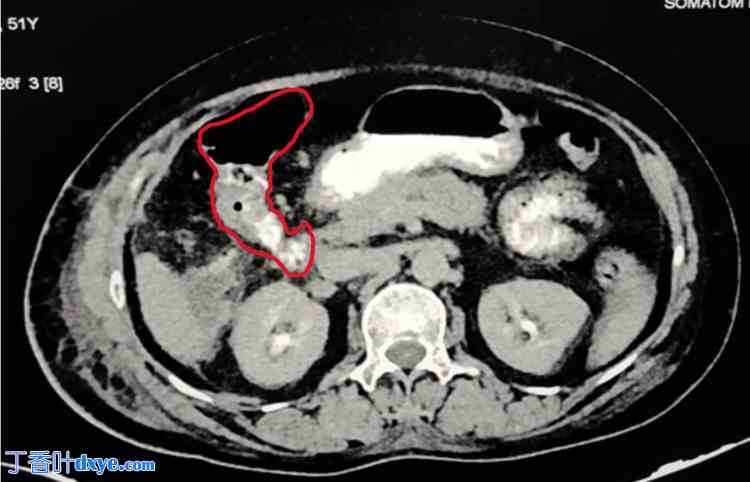

患者接受口服和静脉注射造影剂进行腹部增强 CT 扫描,结果显示胆囊窝内有 2.6 x 2.3 x 2.3 cm 大小的积液(图 1)。积液中可见气液水平。口服造影剂后,十二指肠第二部分与肝曲之间存在可疑连通,因为造影剂在完全遮盖回盲部和盲肠之前已到达横结肠。此外,还发现了一条从肝曲延伸至胆囊窝的线性通道,该通道充满造影剂,长度约为 6.3 mm。

图 1. 增强扫描显示造影剂从横结肠泄漏到胆囊窝。